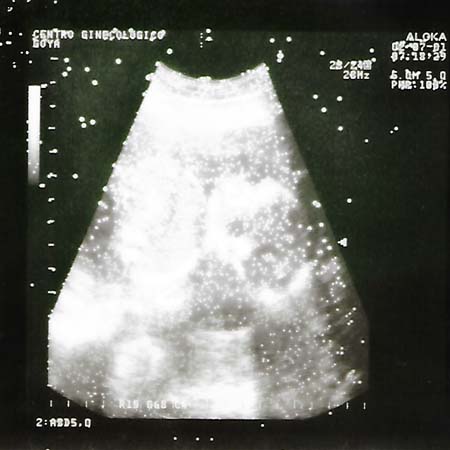

001-ecografia.jpg